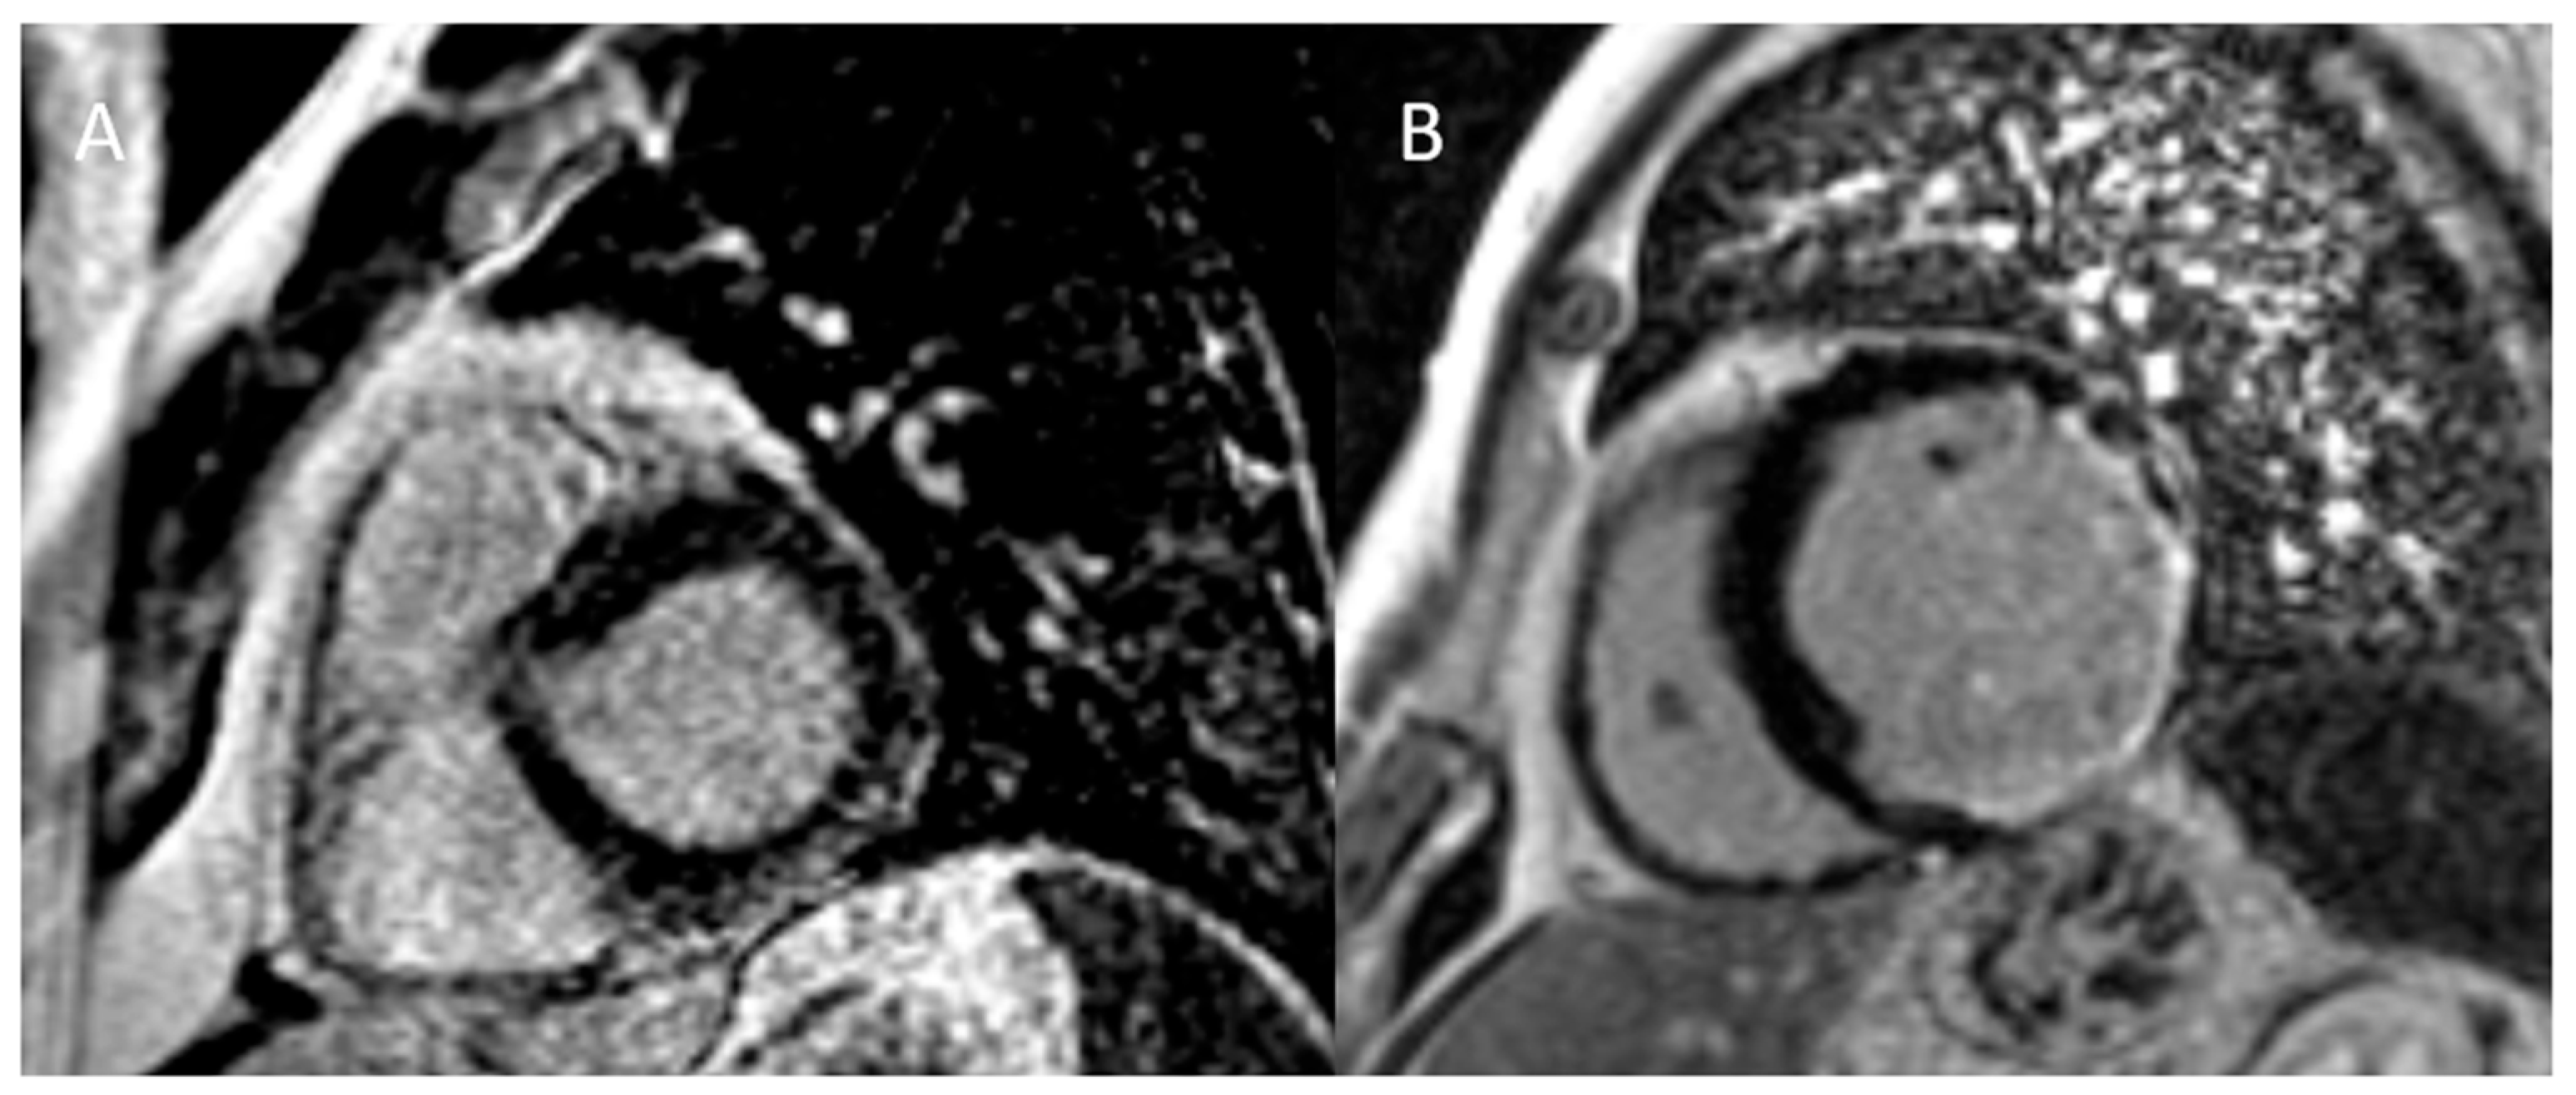

- Matusik, P.S.; Bryll, A.; Matusik, P.T.; Popiela, T.J. Ischemic and non-ischemic patterns of late gadolinium enhancement in heart failure with reduced ejection fraction. Cardiol. J. 2021, 28, 67–76. [Google Scholar] [CrossRef]